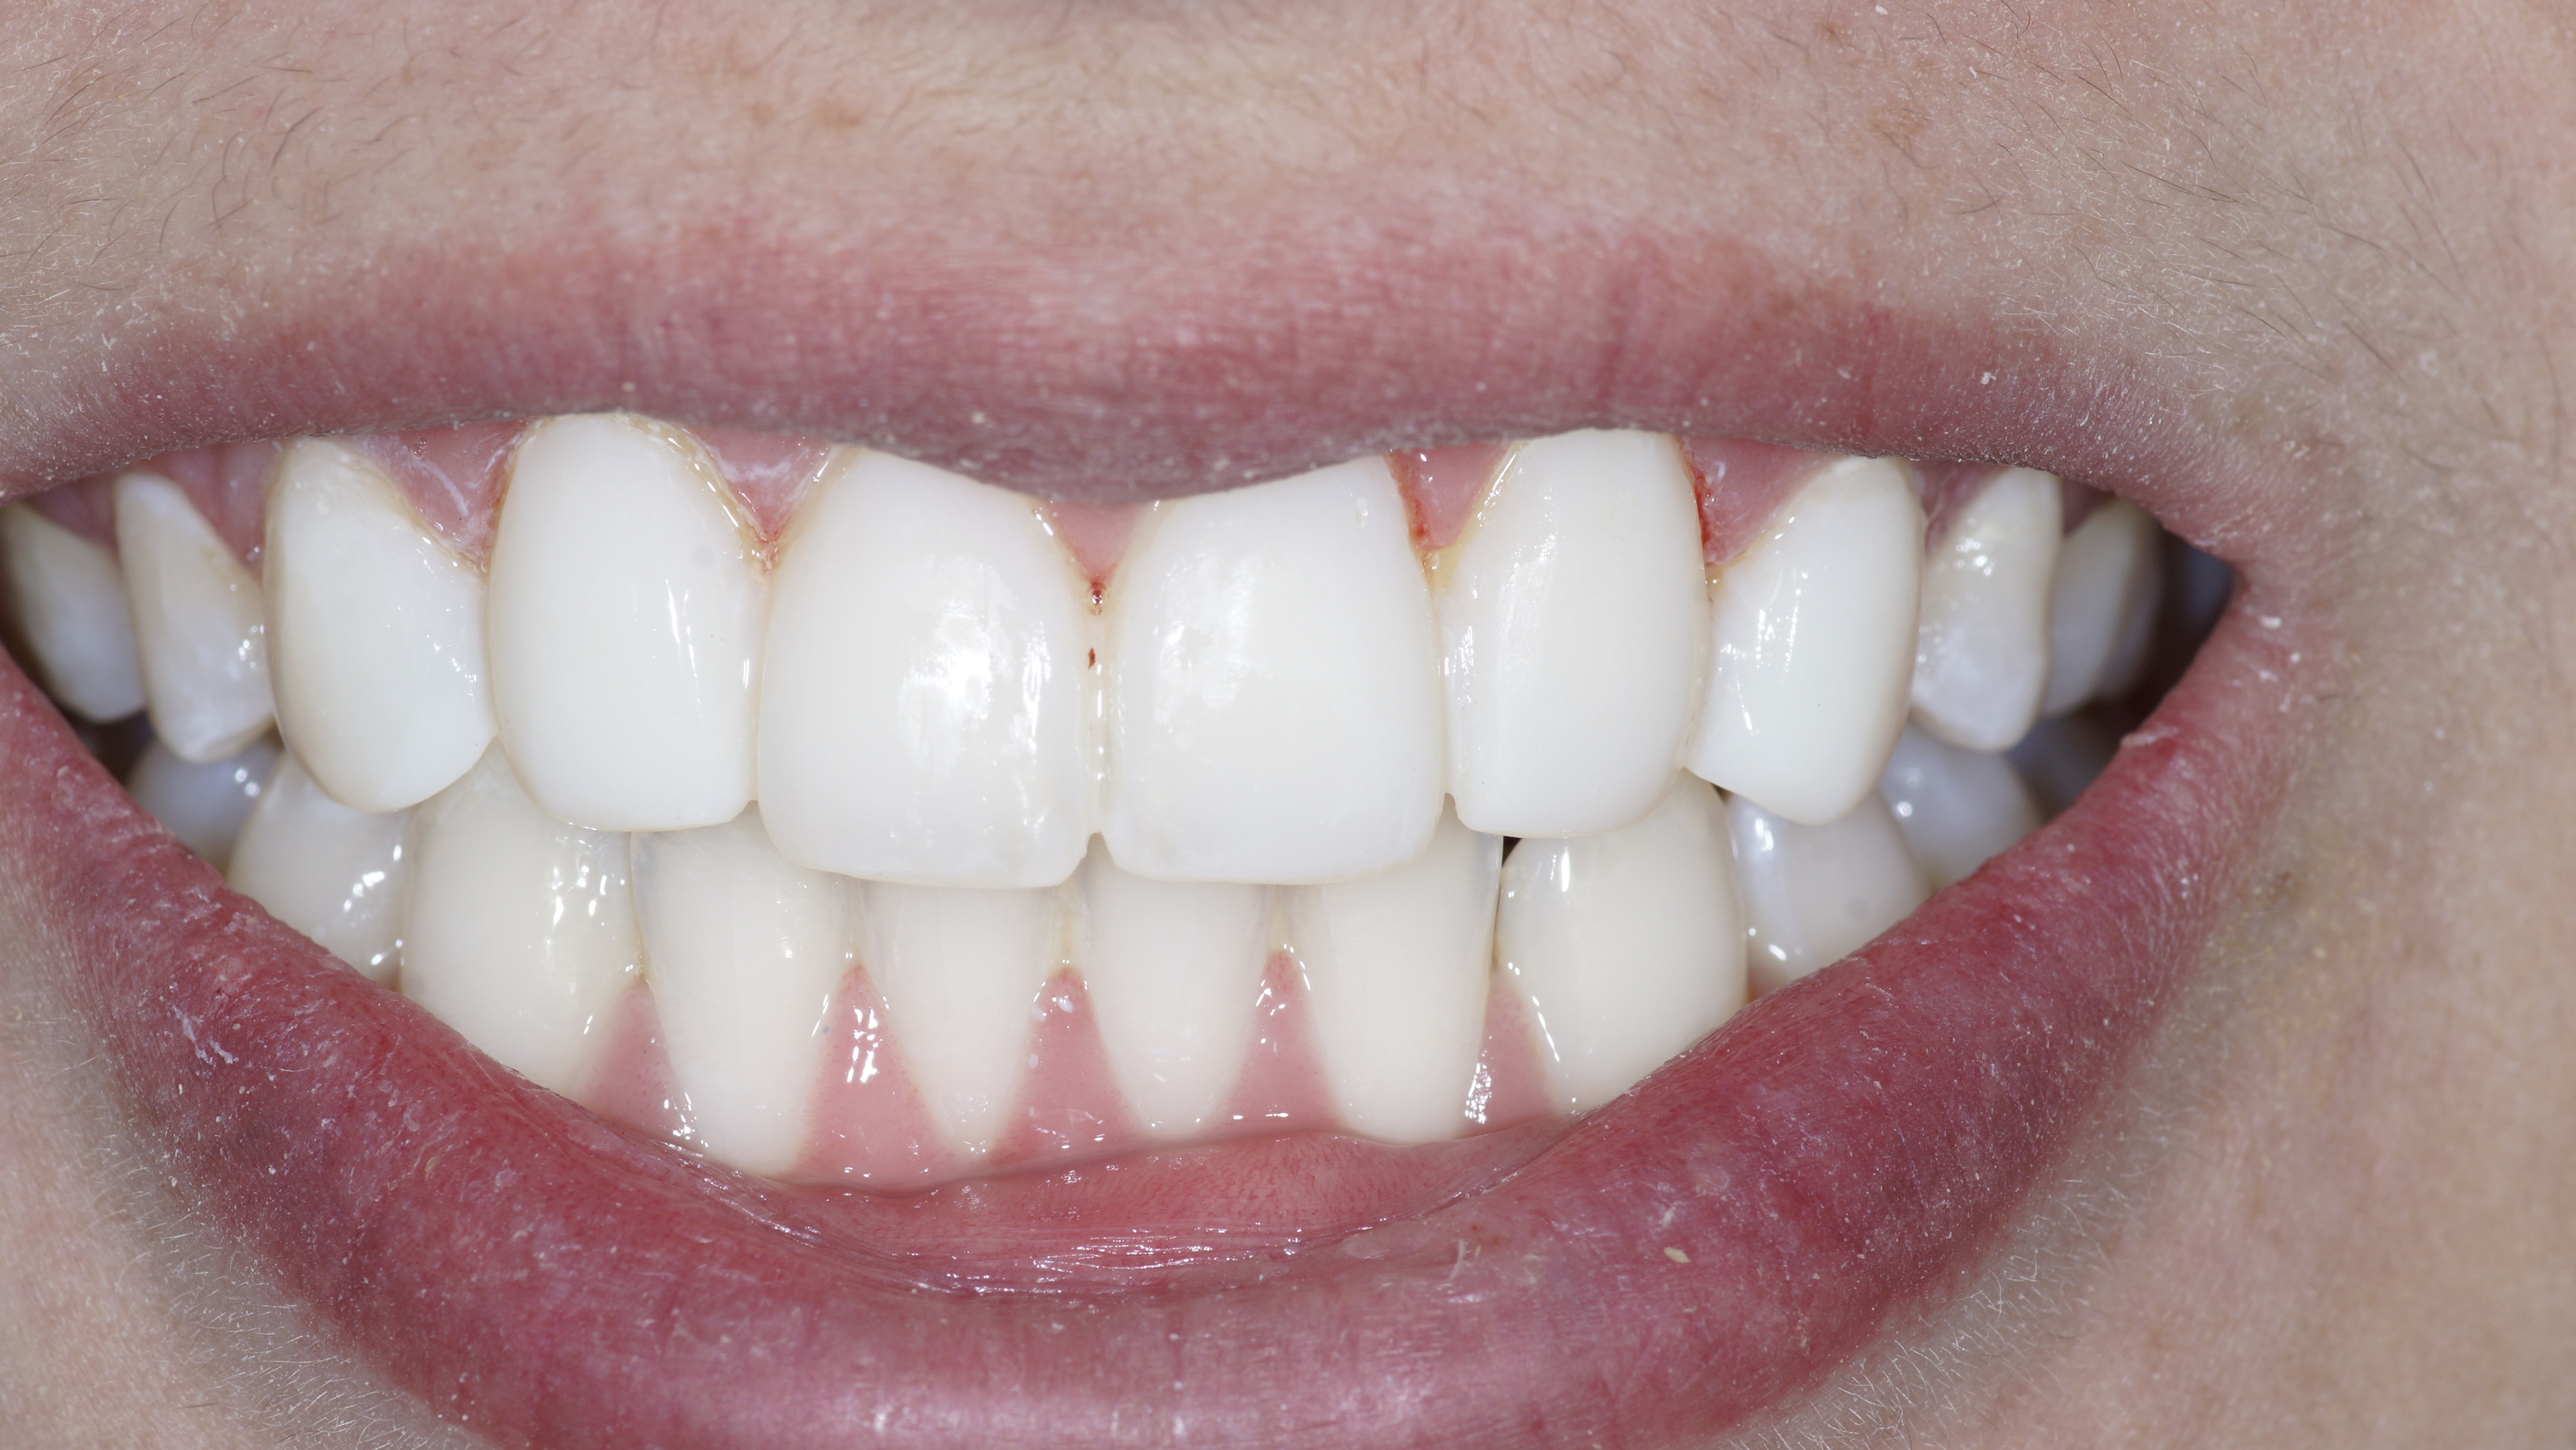

Before